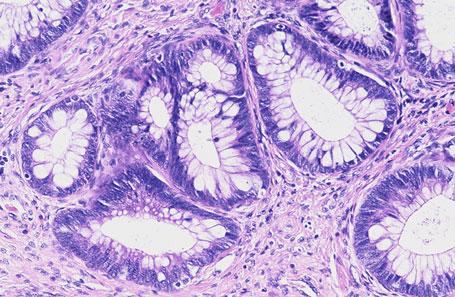

Cechy cytologiczne: Gruczoły szyjki macicy wyścielone są przez nieprawidłowe, kolumnowatego kształtu komórki gruczołowe (Fot. 1). Pod względem cytologicznym przypominają one raka gruczołowego inwazyjnego. Ich jądra komórkowe są hiperchromatyczne, wydłużone, cygarowatego kształtu i posiadają grube ziarnistości chromatyny. Stosunek jądrowo-cytoplazmatyczny przesunięty jest na rzecz jądra. W cytoplazmie występują złogi śluzu wewnątrzkomórkowego (Fot. 2). Patologiczne figury podziałów mitotycznych… Dowiedz się więcej: Gruczolakorak in situ szyjki macicy (łac.: adenocarcinoma in situ [AIS] colli uteri) - Pracownia Genetyki i Biologii Molekularnej